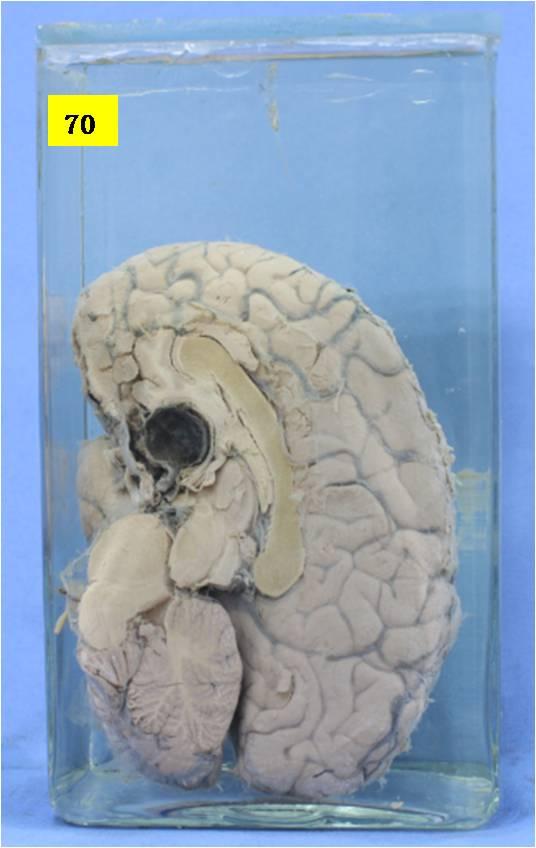

神经疾病-65-70. 垂体出血(卒中)

大脑矢切见垂体部位呈一黑色血凝块,周围胞膜完整。